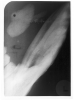

Occlusal radiography is a supplementary radiographic examination designed to provide a more extensive view of the maxilla and mandible.

The occlusal image, as seen in Figure 3, is very useful in determining the buccolingual extension of pathologic conditions and provides additional information as to the extent and displacement of fractures of the mandible and maxilla. Occlusal radiographic images also aid in localizing unerupted teeth, retained roots, foreign bodies, and calculi in the submandibular and sublingual salivary glands and ducts. It should be noted that when imaging soft tissues, exposure time needs to be appropriately reduced.

Figure 3 - Occlusal Images

Figure 3